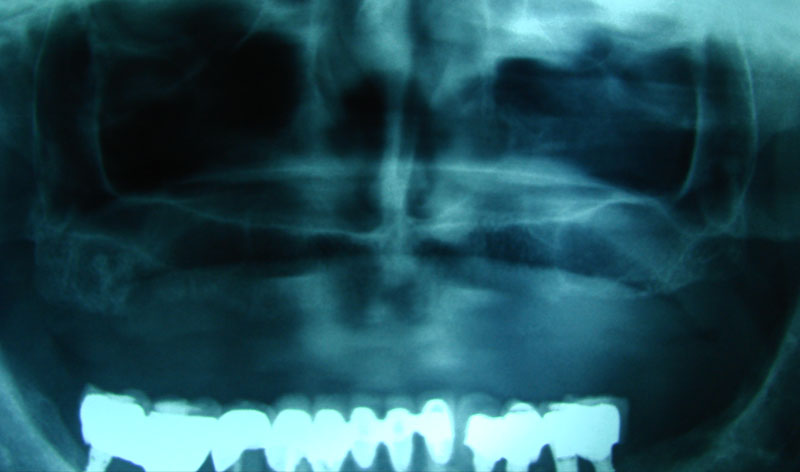

Existen muchas situaciones donde la pérdida y la atrofia ósea son tan graves que nos obligan a recurrir a la cresta iliaca del paciente, para conseguir el volumen óseo necesario para la correcta reconstrucción del maxilar. Así, la colocación de implantes será posible a los 3 meses.